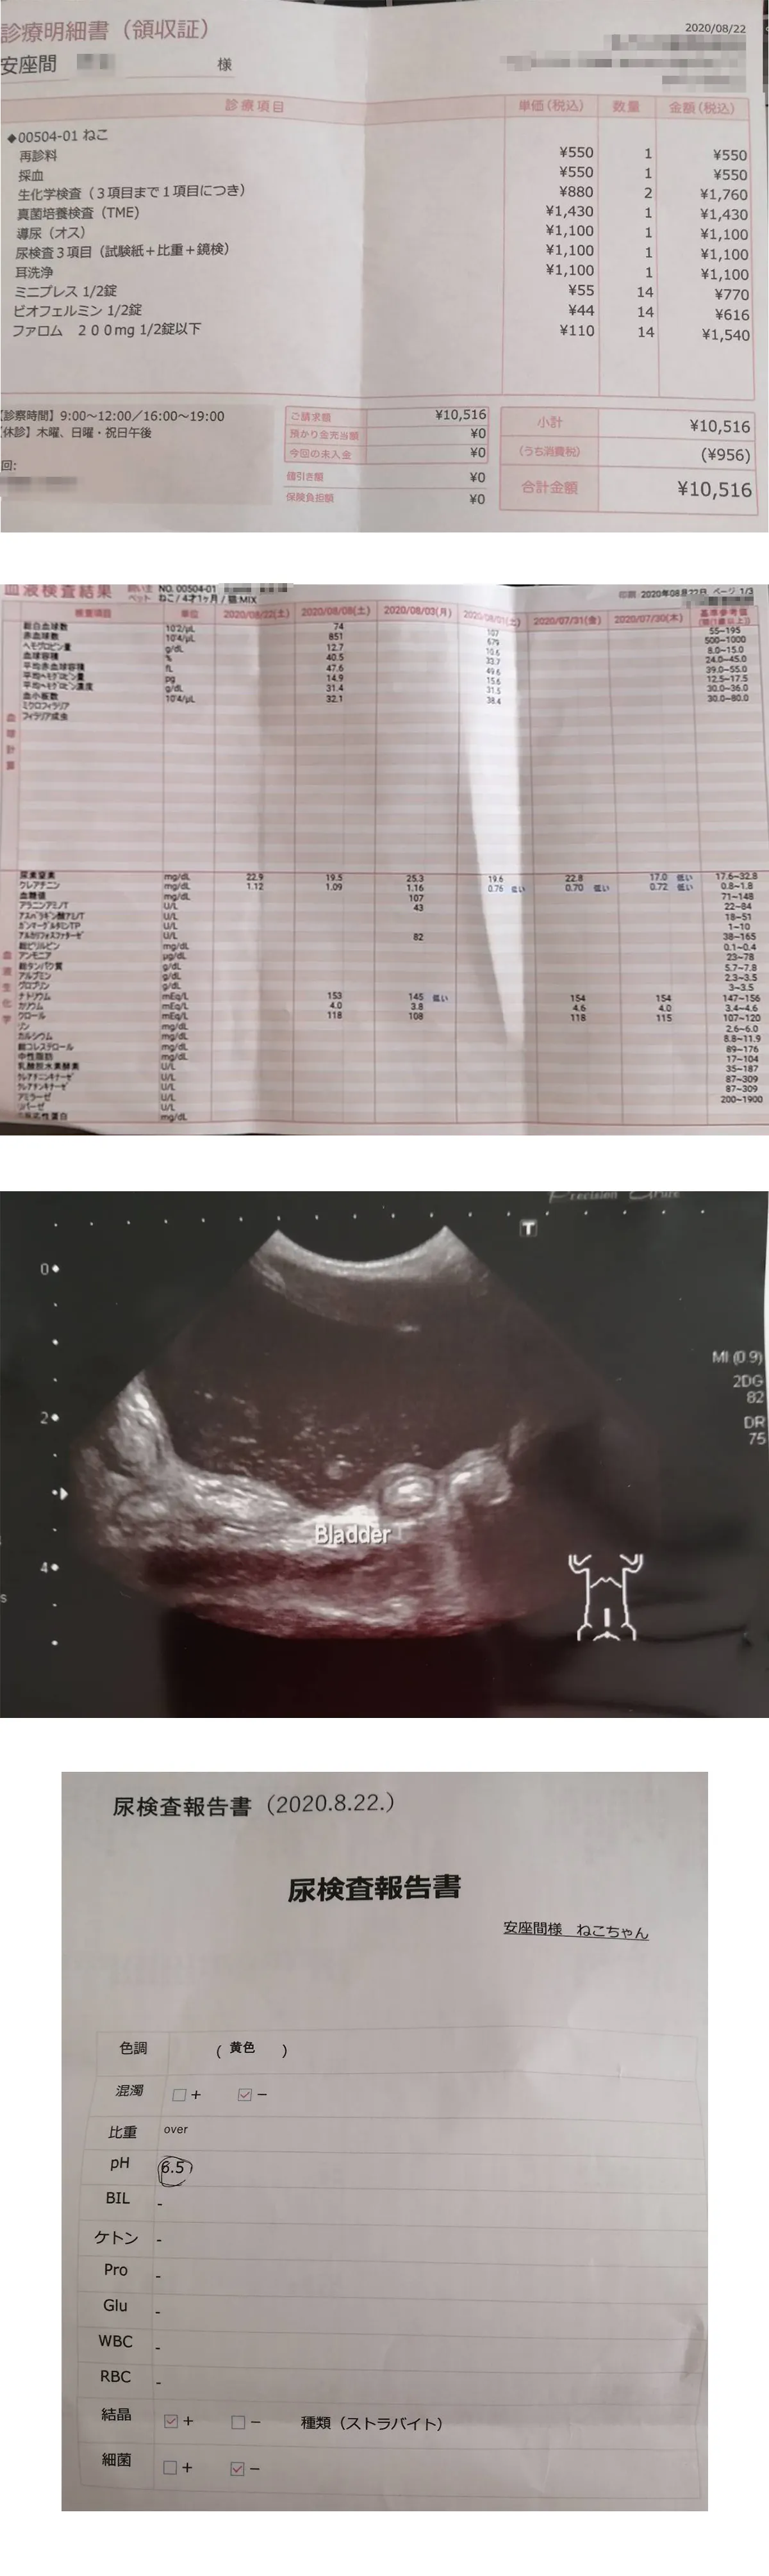

膀胱炎の細菌の状態と一度治まった腎数値の悪化が再発していないかの確認の為、血液検査を行いました。

腎数値は正常値で腎不全の問題はなし。

膀胱炎に関しては、先週抗生剤を変えたことによる効果で細菌はほぼ死滅していました!!!

膀胱に尿結晶が存在していました。

どうやら膀胱炎の影響のようで、このまま結晶が成長すると結石となってしまうようです。

しかし、幸いなことに結晶の成分?がストラバイトというものでした。

これは、溶かすことが出来る結晶で今後の治療や食事療法により結晶を消滅させることが可能です。

治療方法としては、引続き抗生剤で菌の増殖を抑える。排尿補助のお薬と飲水量を増やして排尿サイクルを早め膀胱を良好に保つ事となります。